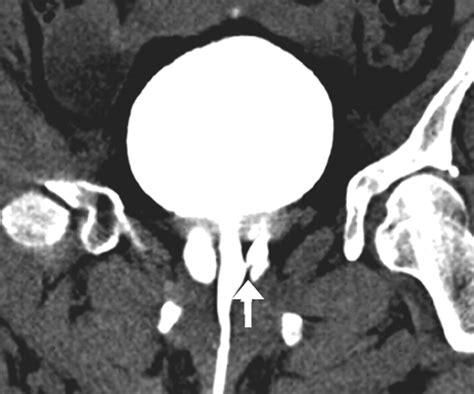

Diagnosis requires a high index of suspicion, especially when standard treatments for UTIs fail. A physician will typically perform a physical exam, which may reveal a tender mass along the anterior vaginal wall. If pressure is applied to the mass, it is not uncommon for a small amount of urine or purulent discharge to exit the urethra.

MRI (Magnetic Resonance Imaging) The gold standard for visualizing the size and location of the diverticulum.

Voiding Cystourethrogram (VCUG) Uses contrast dye to see if the pouch fills during urination.

Urethroscopy Direct visualization of the urethra using a thin camera to locate the diverticular opening.